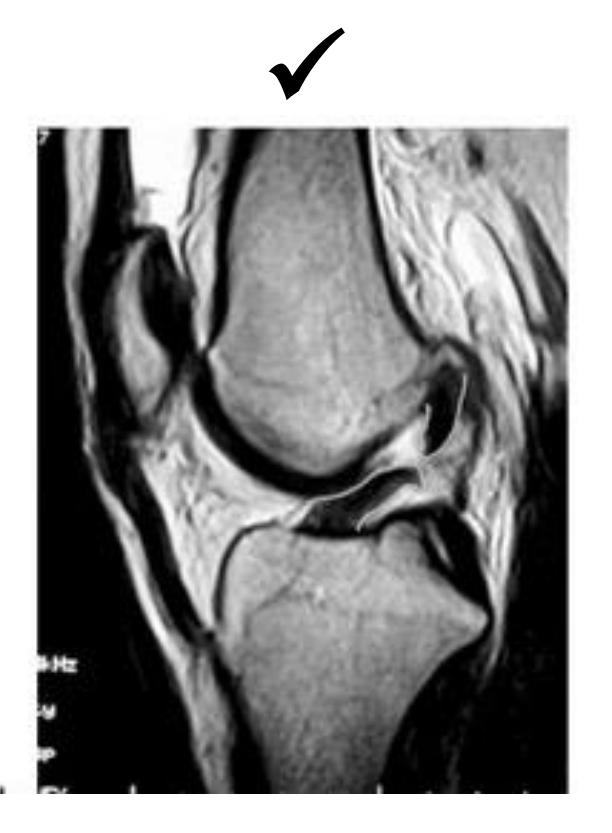

What is the imaging modality and diagnosis?

- Modality: MRI

- Diagnosis: ACL tear

What finding is shown in this MRI?

-

Torn ACL